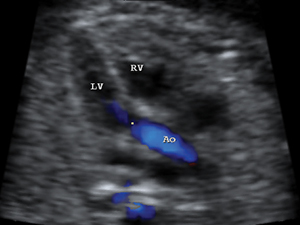

Aortic outflow tract with colour indicating the flow